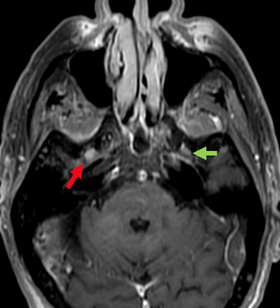

The imaging workup included MRI of the paranasal sinuses and brain, which showed a lesion in the right cavernous sinus with enhancement in the path of the right maxillary (V2), vidian, and mandibular (V3) nerves, consistent with perineural tumor spread (Figure 1) (Figure 2).

Figure 1 Magnetic resonance imaging, T1-weighted sequence with fat suppression. Coronal slices showing anomalous contrast enhancement in the foramen rotundum (red arrow) and pterygoid canal (blue arrow).

Figure 2 Magnetic resonance imaging, T1-weighted sequence with fat suppression. Axial slices showing anomalous contrast enhancement in the right foramen rotundum (red arrow), normal on the left (green).